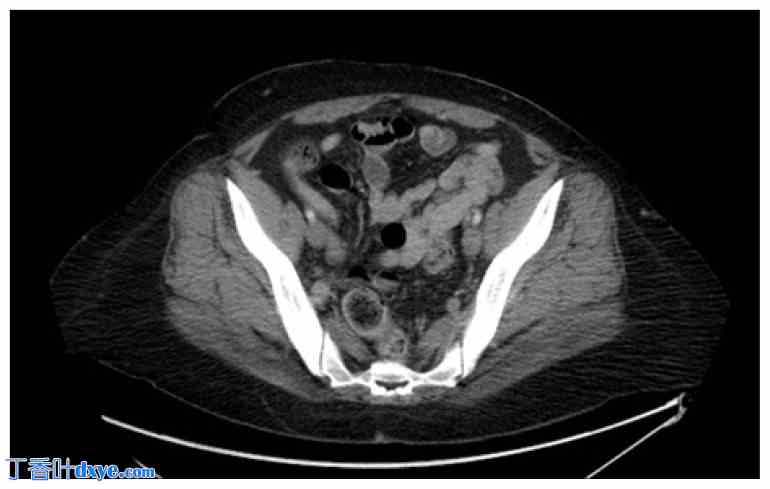

经阴道超声检查显示子宫已被切除。右侧卵巢未见显影。左侧卵巢尺寸为4.4 x 3.7 x 5.0厘米。检测到左侧卵巢静脉血流,但难以获得动脉血流。左侧卵巢囊肿较小,大小为 2.2 x 1.9 x 2.2 厘米,形态简单。左侧卵巢中央可见一回声区,大小为 3.6 x 2.8 x 3.0 厘米。未见附件肿块或盆腔积液。膀胱未见异常(图 1 和图 2)。

经阴道彩色多普勒超声检查左卵巢,显示卵巢囊肿(箭头)。